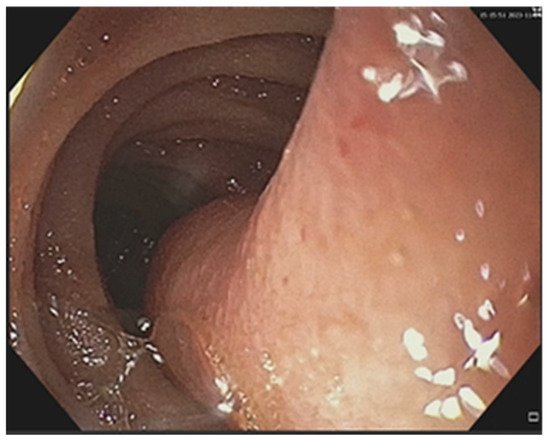

3. Results

3.2. Treatment Particularities